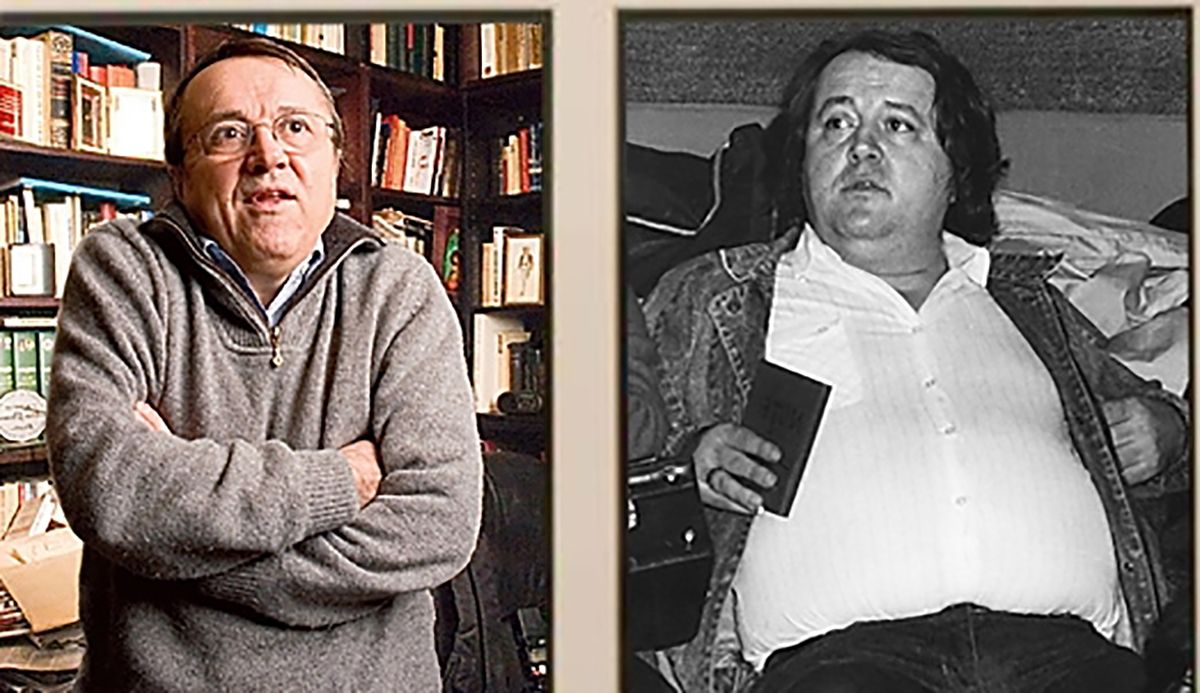

Noile descoperiri sunt cele mai recente din laboratorul lui Jonathan Kipnis, dr., care a făcut o descoperire uimitoare în timp ce era la UVA în 2015 că creierul a fost conectat la sistemul imunitar de către vase despre care se credea că nu există.